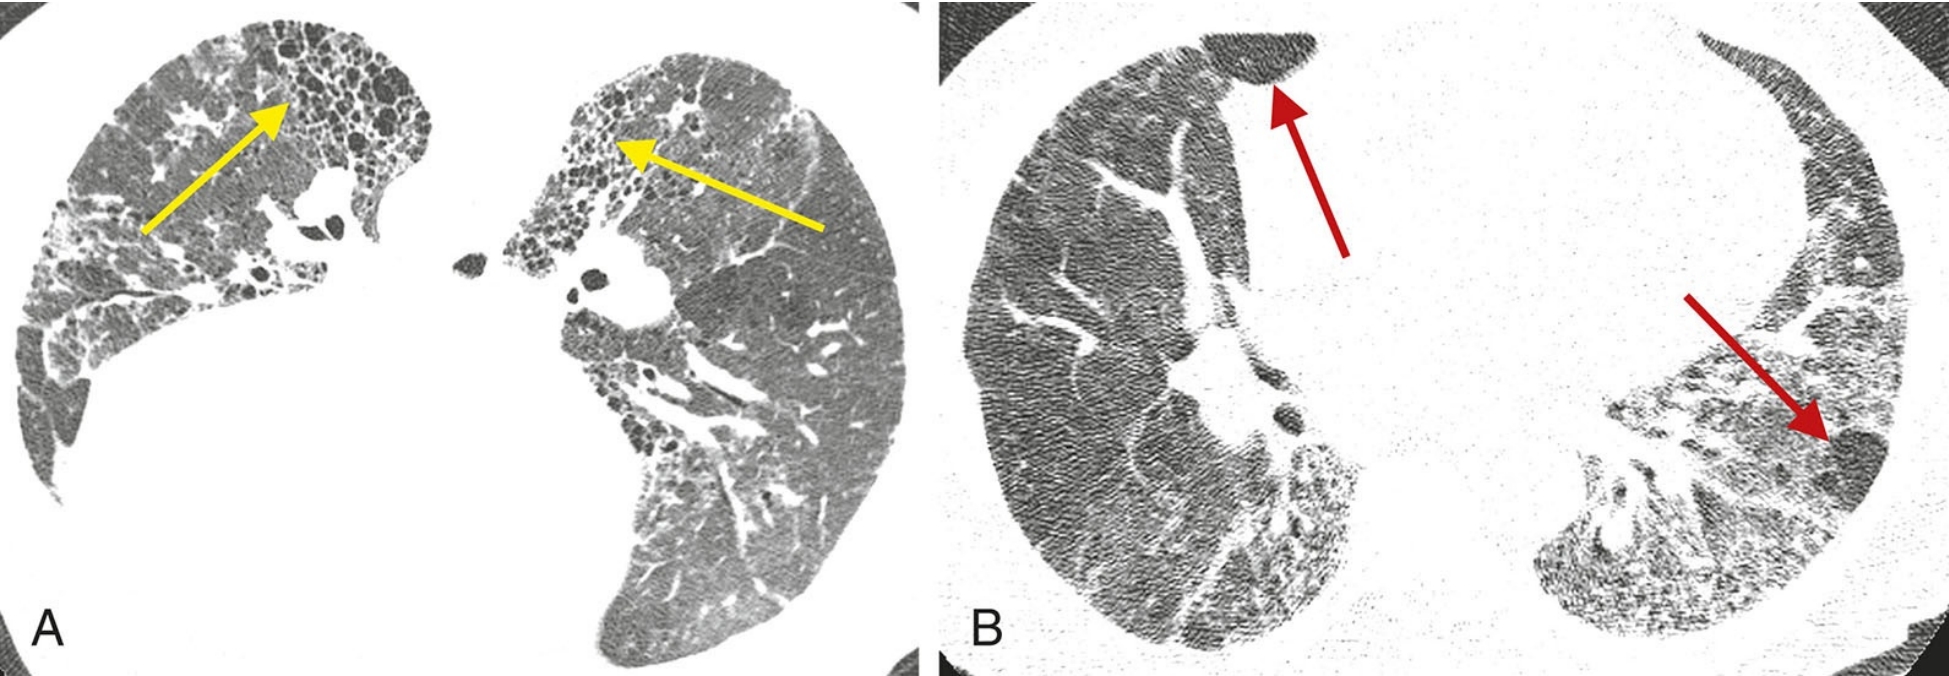

eb8e21eebff9ef7cc5bf91aa43df6ecf.png

炎症与纤维化的HRCT不同表现。

间质性肺炎表现为不同程度的炎症和纤维化;A和B. 2例结缔组织病患者的非特异性间质性肺炎。

A.HRCT显示GGO,无明显的纤维化征象,提示潜在可逆的炎症性病变;

B.HRCT显示牵拉性支气管扩张(箭)及不规则网状影的纤维化征象,提示对治疗不敏感的肺部瘢痕。